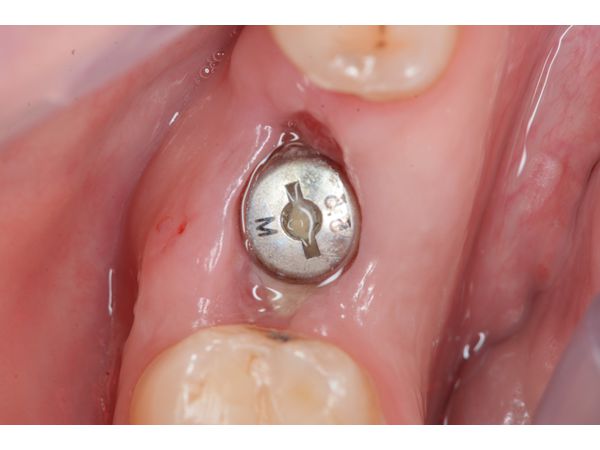

Через две недели произведено снятие швов. Пациент отметил отсутствия боли и дискомфорта в зоне установленного имплантата. В период заживления выполнял все рекомендации и соблюдал гигиену полости рта.

Через три месяца пациент направлен на протезирование к стоматологу-ортопеду. На контрольном осмотре через три месяца пациент сообщил, что за всё это время возникновение боли и дискомфорта в области имплантата не отмечал. Также он отметил, что сама процедура прошла легко, безболезненно и с комфортом.